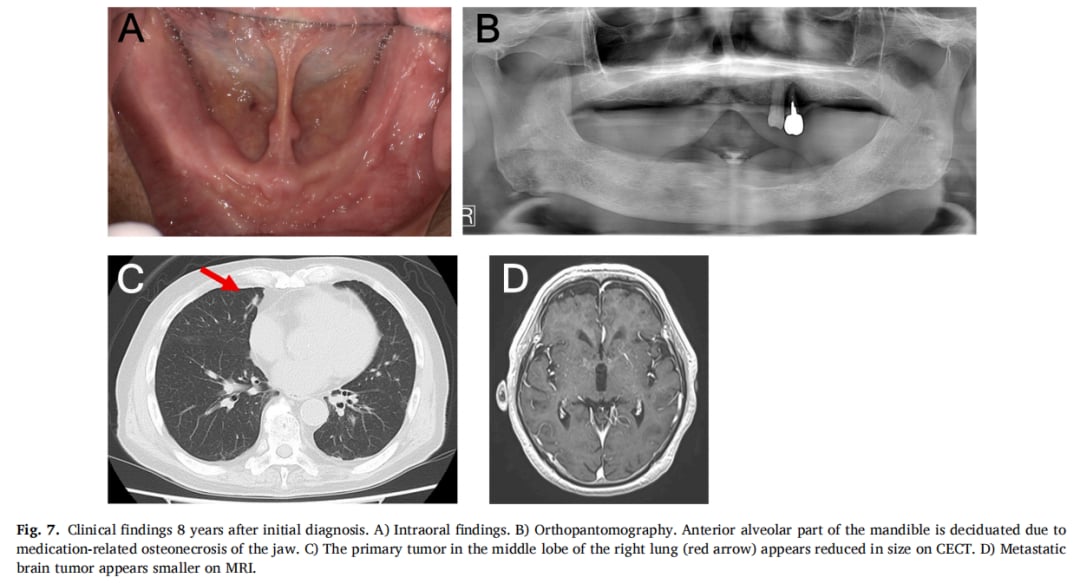

▲图7 初次诊断8年后的临床表现

值得一提的是,在长期治疗过程中,患者曾因使用地诺单抗出现了药物相关的颌骨坏死,但在停药并接受相应处理后,该副作用也得到了有效控制。这表明,在长期治疗中,对副作用的监控和管理同样重要。